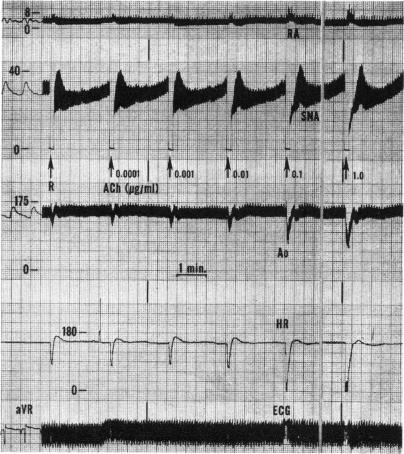

Cardiac innervation: anatomic and pharmacologic relations.